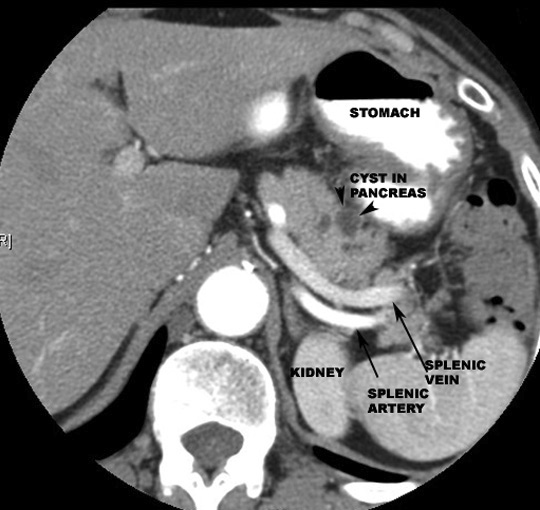

- Body

- Anterior

- Stomach separated by omental bursa

- Posterior

- Aorta

- SMA

- Left crus of diaphragm

- Left adrenal

- Left kidney

- Left renal vein

- Splenic vein